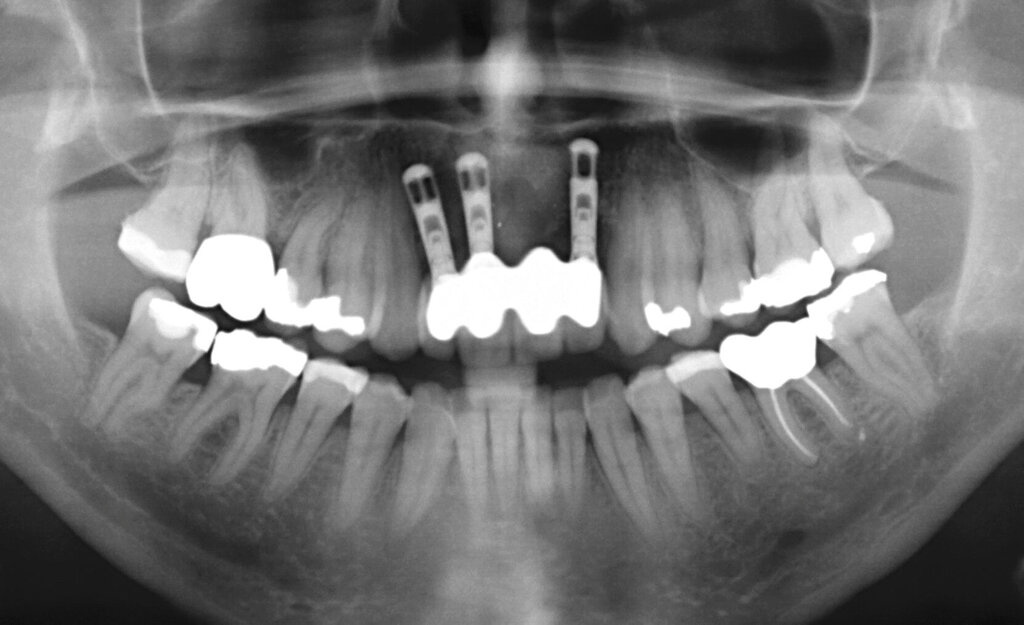

Nachdem der Patient bei einem Berufsunfall mit Ausnahme der zweiten Molaren und der Weisheitszähne alle Zähne im Unterkiefer verloren hatte, erfolgte 1996 im Alter von 44 Jahren die definitive Lückenversorgung. Hierzu wurden eine verschraubte Brückenkonstruktion (044-034-043-044) sowie zwei verblockte Kronenpaare auf insgesamt acht Implantaten eingesetzt. Nach sieben Jahren Tragedauer wurde an mehreren Implantaten röntgenologisch ein Knochenabbau festgestellt. Verkürzte Kontrollintervalle mit professionellen Zahnreinigungen und intensiven Instruktionen zur Interdentalhygiene konnten nicht verhindern, dass nach weiteren sieben Jahren Anfang 2011 der Knochenverlust an den meisten Implantaten auf 50 bis 80 Prozent zunahm (Abb. 1a).

Die Entscheidung zur Explantation fiel wegen des beschleunigten Knochenverlusts und der extrem erschwerten Bedingungen für eine effektive Mundhygiene im Bereich der Implantate mit Sondierungstiefen bis zu 12 mm (Abb. 1b und 1c). Unter Lokalanästhesie wurden sieben der acht Implantate mit einem passenden Trepanbohrer mit 0,1 mm Aufmaß im Vergleich zum Außendurchmesser der Implantate umbohrt, anschließend mit einem kleinen Rasparatorium gelockert und dann mit einer Arterienklemme entfernt. Entscheidend für die Eignung der Trepanbohrer war die Längenmarkierung, um eine Nervverletzung bei der Entfernung der sehr tief gesetzten Seitenzahnimplantate zu vermeiden (Abb. 1d und 1e). Eine ausgedehnte Lappenbildung konnte durch dieses Vorgehen vermieden werden.